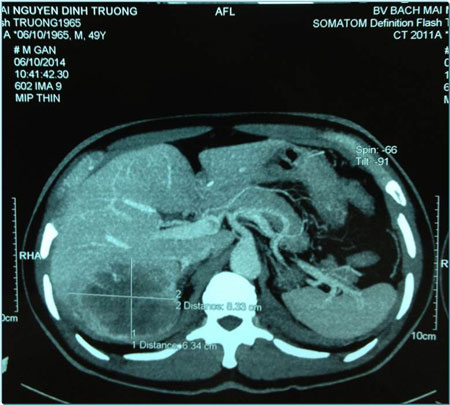

Hình ảnh khối u thu nhỏ còn 3,0 x 3.5cm sau điều trị bằng hạt vi cầu phóng xạ.

“Với khối u lớn như vậy sẽ không thể phẫu thuật. Vì thế, chúng tôi đã quyết định sử dụng phương pháp hạt vi cầu phóng xạ để giảm kích thước khối u cho người bệnh. Kết quả sau điều trị kích thước khối u giảm xuống còn 3,0x3,5cm. Lúc này bác sĩ mới có thể can thiệp phẫu thuật cắt bỏ đoạn TT lấy u gan di căn”, TS Thái cho biết.